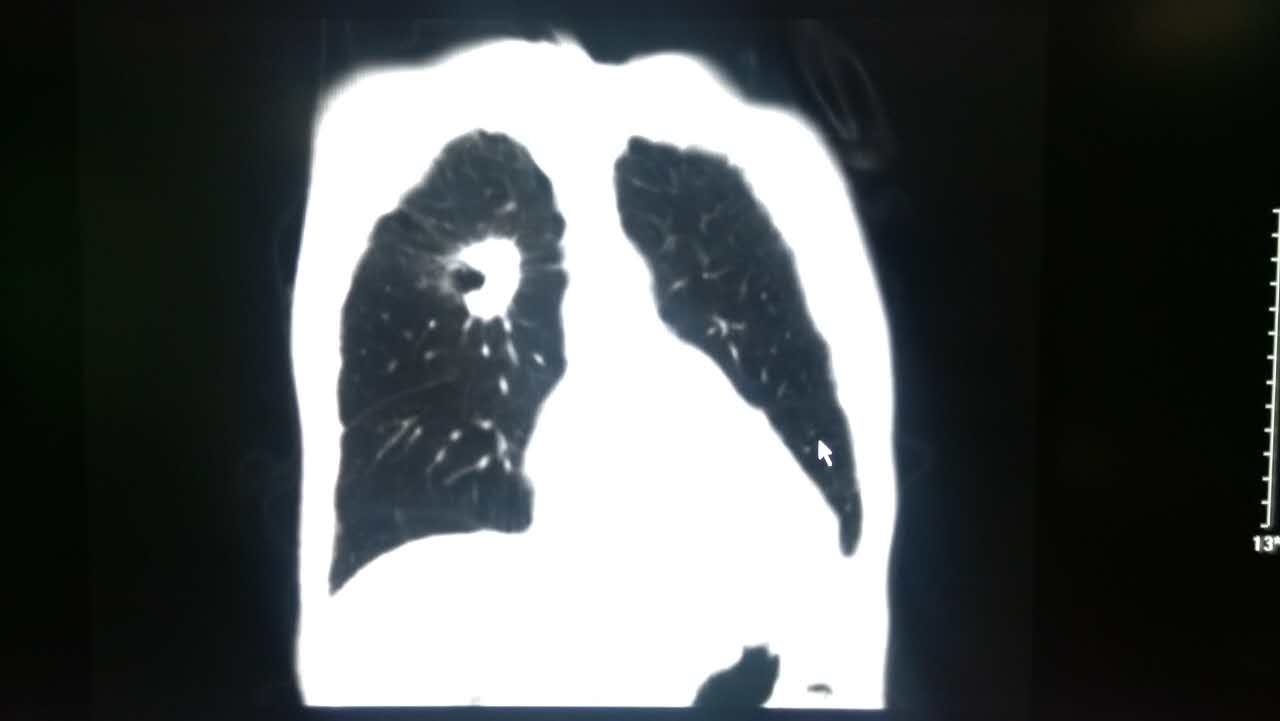

支气管肺癌ct图片

支气管肺癌ct图片,肺癌ct图片

胸部ct:右主支气管内椭圆形肿块影,可见明显阻塞性肺炎,肺不张表现.